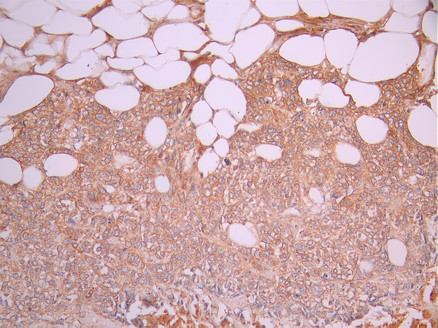

• IHC image of CSB-RA270243A0HU diluted at 1:100 and staining in paraffin-embedded human tonsil tissue performed on a Leica BondTM system. After dewaxing and hydration, antigen retrieval was mediated by high pressure in a citrate buffer (pH 6.0). Section was blocked with 10% normal goat serum 30min at RT. Then primary antibody (1% BSA) was incubated at 4°C overnight. The primary is detected by a Goat anti-rabbit polymer IgG labeled by HRP and visualized using 0.05% DAB.